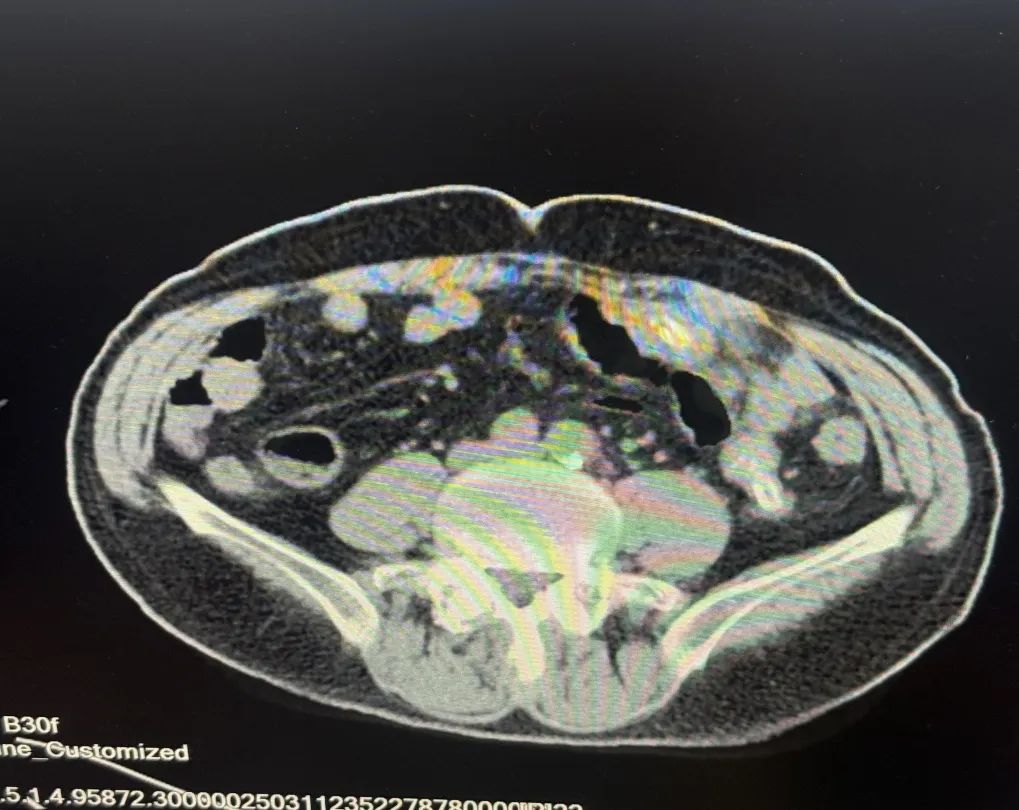

内容提要 从盘锦到葫芦岛,跨越180公里的生命接力中,葫芦岛市第二人民医院胃肠外科刘万忠主任团队用精准的治疗方案和手术技术,为晚期胃癌患者点燃了新的生命希望。 Part.01 隐秘的危机 从食欲骤降到癌魔突袭 2024年深冬,一向健朗的张大爷突然茶饭不思,短短半月暴瘦12斤。胃镜图像触目惊心:食管下段至胃窦广泛紫红色病变、胃壁僵硬、胃底后壁近贲门见不规则隆起溃疡性病变,表面污秽苔及陈旧血痂附着。病理结果明确指向“胃低分化癌”,更令人担忧的是,增强MR显示癌细胞已经扩散到淋巴结,腹腔多发转移,这一结果更让病情雪上加霜。三次化疗未能遏制病情,子女们近乎绝望:“难道真的没有希望了吗?” 患者术前胃部影像 Part.02 从绝望到希望 两城辗转中的诊疗抉择 转机出现在葫芦岛亲戚的建议下:“来我们这儿的市二院看看吧,多看一家医院就多一份希望”。胃肠外科刘万忠主任仔细翻阅厚厚的检查资料后,向家人说出了自己的想法:“虽然病情复杂,但精准的手术干预仍有延续生命的希望。”这一判断像黑暗中的一束光,点燃了全家的希望。最终确定手术方案为“胃恶性肿瘤根治术(全胃切除伴食管空肠吻合术+空肠侧侧吻合术+区域淋巴结切除术)”。 Part.03 硬核技术权威支撑 手术台上的生死博弈 面对这个被多家医院判定“不可切除”的病例,刘万忠主任团队展现了区域顶尖医疗团队的实力:术中见肿瘤如蛛网般蔓延胃底胃体,侵蚀胃小弯及胃角,胃周可见肿大淋巴结,已浸及全层,与周围组织形成致密粘连。肿大淋巴结包绕重要血管,稍有不慎即引发致命性出血,既要彻底清除肿瘤,又要保留消化功能,这对吻合技术提出极限挑战。历经4小时鏖战,刘万忠主任团队不仅完整切除病灶,更通过精细的消化道重建,最大限度保留了患者术后生活质量。 术后第3天,张大爷已能经口进食米汤;两周后,他带着定制的营养食谱和康复管理手册出院。出院时,他紧握刘万忠主任的手哽咽道:“是你们给了我第二次生命!” 刘万忠主任深耕胃肠肿瘤领域近30年,已完成胃结直肠及肛肠等各类手术万余例,其中胃结直肠等三四级手术3000余例。在刘万忠主任带领下,科室已与中国医学科学院肿瘤医院、北京中日友好医院、中国医科大学附属第一医院、中国医科大学附属盛京医院、辽宁省肿瘤医院、锦州医科大学附属医院建立合作,可提供一站式专家看诊、手术及国内名院转诊服务。科室以胃及结直肠微创手术为特色,可开展多种疑难和高难手术,越来越多曾被视为“没希望”的患者,在这里找到了新生的可能。 Part.04 人民医院 人民名医 刘万忠 主任医师 硕士研究生 ·葫芦岛市第二人民医院胃肠外科主任 ·世中联盆底专业委员会委员 ·世中联虚实挂线委员会委员 ·中日友好医院肛肠专科医联体专家委员会委员 ·中国研究型医院学会腹膜后与盆底专业委员会青年委员 ·中国人体健康促进会甲状腺肿瘤专业委员会委员 ·辽宁省中西医结合肛肠委员会委员 ·东三省肠内外营养专业委员会委员 ·大连市中西医结合学会乳甲专业委员会常委 专业特色:从事胃肠肿瘤外科领域近三十年,在国内知名三甲医院担任普外科主任、学科带头人10余年。先后在中国医科大学附属二院、北京301医院、北京医科大学附属三院、中日友好医院、哈尔滨医科大学附属二院进修学习。擅长胃癌、结直肠癌、胃肠间质瘤等胃肠肿瘤及肛肠复杂疾病诊治。 精通普外科腹腔镜微创技术、独立开展普外科腹腔镜手术包括:腹腔镜阑尾切除术(LA)、腹腔镜疝修补术(TAPP)、腹腔镜结直肠癌根治术及腹腔镜直肠癌NOSES手术等高难度手术,已完成胃结直肠及肛肠等各类手术万余例,其中胃结直肠等三四级手术3000余例。主持吴阶平基金会科技部《FH检测技术在直肠癌超早期筛查中的临床意义》临床科研课题项目一项。在国内外行业杂志发表论文10余篇,参与编撰专著2部。